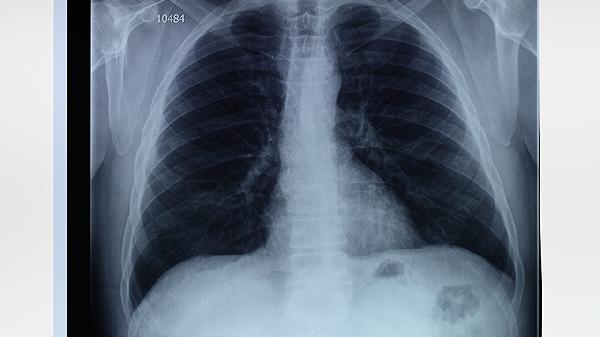

患者常见活动后气促、慢性咳嗽等症状,但无发热、咳脓痰等感染征象。影像学检查可见肺过度充气、肺大泡形成等特征,与传染性肺炎的渗出性病变存在本质区别。